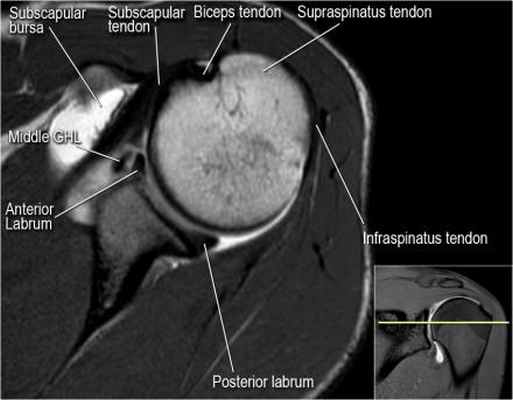

Изображение задних отделов плечевого сустава.

Отображены надостная, подостная и малая круглая мышцы и их сухожилия. Все они прикрепляются к большому бугорку плечевой кости. Сухожилия и мышцы манжеты вращателей участвуют в стабилизации плечевого сустава во время движения. Без манжеты вращателей головка плечевой кости частично сместилась бы из суставной впадины, уменьшив силу отведения дельтовидной мышцы (мышцы вращательной манжеты координирует усилия дельтовидной мышцы). Повреждение манжеты вращателей может привести к смещению головки плечевой кости кверху, в результате вызвая высокое стояние головки плечевой кости.

Нормальная анатомия плечевого сустава в аксиальных изображениях и контрольный список.

- уровень средней плече-лопаточной связки и передних отделов суставной губы. Поищите комплекс Буффорда. Изучите хрящи.

- вогнутость заднебокового края головки плечевой кости не следует путать с повреждением Хилл-Сакса, поскольку это нормальная форма для данного уровня. Повреждение Хилл-Сакса визуализируется только на уровне клювовидного отростка. В предних отделах мы сейчас на урвоне 3-6 часов. Здесь визуализируются повреждение Банкарта и его варианты.